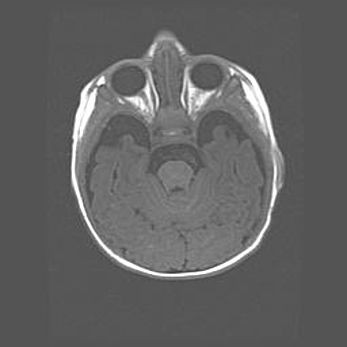

Неполная лизэнцефалия (пахигирия). Открытая гидроцефалия.

Возраст: 17 дней

Вес: 3110 г

Пол: мужской

Окружность головы: 33,5 см

Срок гестации: 35-36 недель

Лизэнцефалия—недоразвитие корковой пластинки и мозговых извилин в результате нарушения миграции нейронов коры. Поверхность мозговых полушарий гладкая. Микроскопически выявляется отсутствие нормальных слоев коры и скопление групп нейронов в подкорковом белом веществе.

Пахигирия—уменьшение числа вторичных извилин. В пораженном полушарии нервные клетки образуют толстый недифференцированный слой с неправильно расположенными нервными волокнами и группами гетеротопных клеток. Нервные клетки незрелые. Белое вещество истончено. При этом нередко аномально развит корково-спинномозговой путь.